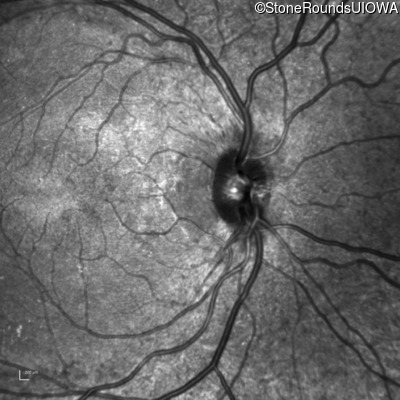

The clinical features supporting the diagnosis of the enhanced S-cone syndrome (ESCS) in this patient include: stable night blindness since at least the second year of life, normally sighted parents, nummular pigment in the mid-periphery of the fundus that stops abruptly at the temporal arcades and disorganization of the retinal layers (seen on OCT) anterior to the temporal arcades.